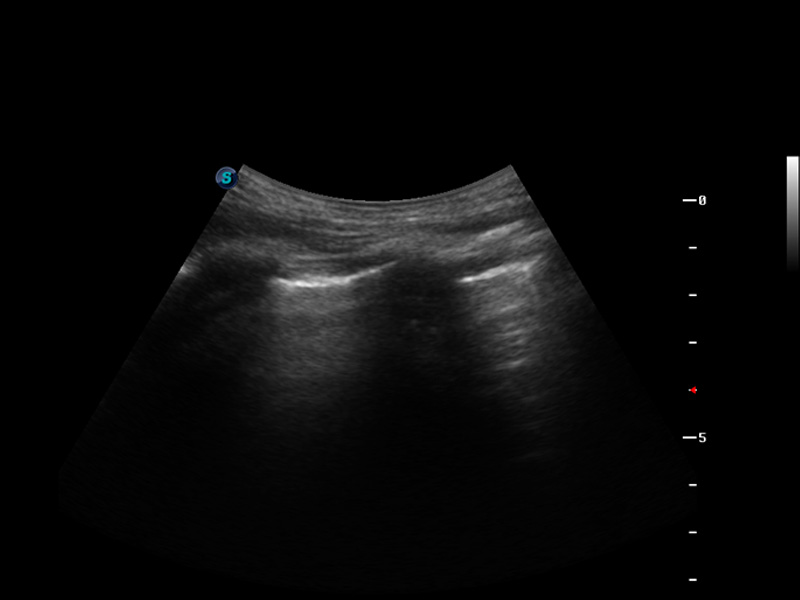

S9便携式彩色多普勒超声诊断仪是乐玩lewin国际研发的高端便携彩超设备,外观设计新颖、产品性能卓越。S9在便携超声领域采用了突破传统的触摸屏交互设计,并以先进的软件硬件技术和设计理念,为您带来清晰的图像质量、稳定的工作性能和便捷的操作体验。